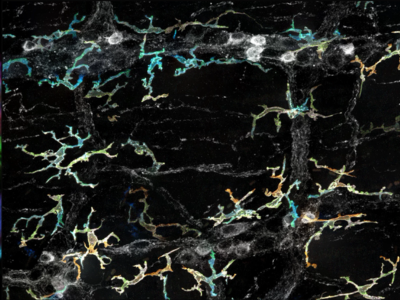

No 5 | Défense immunitaire sur le tissu neuronal